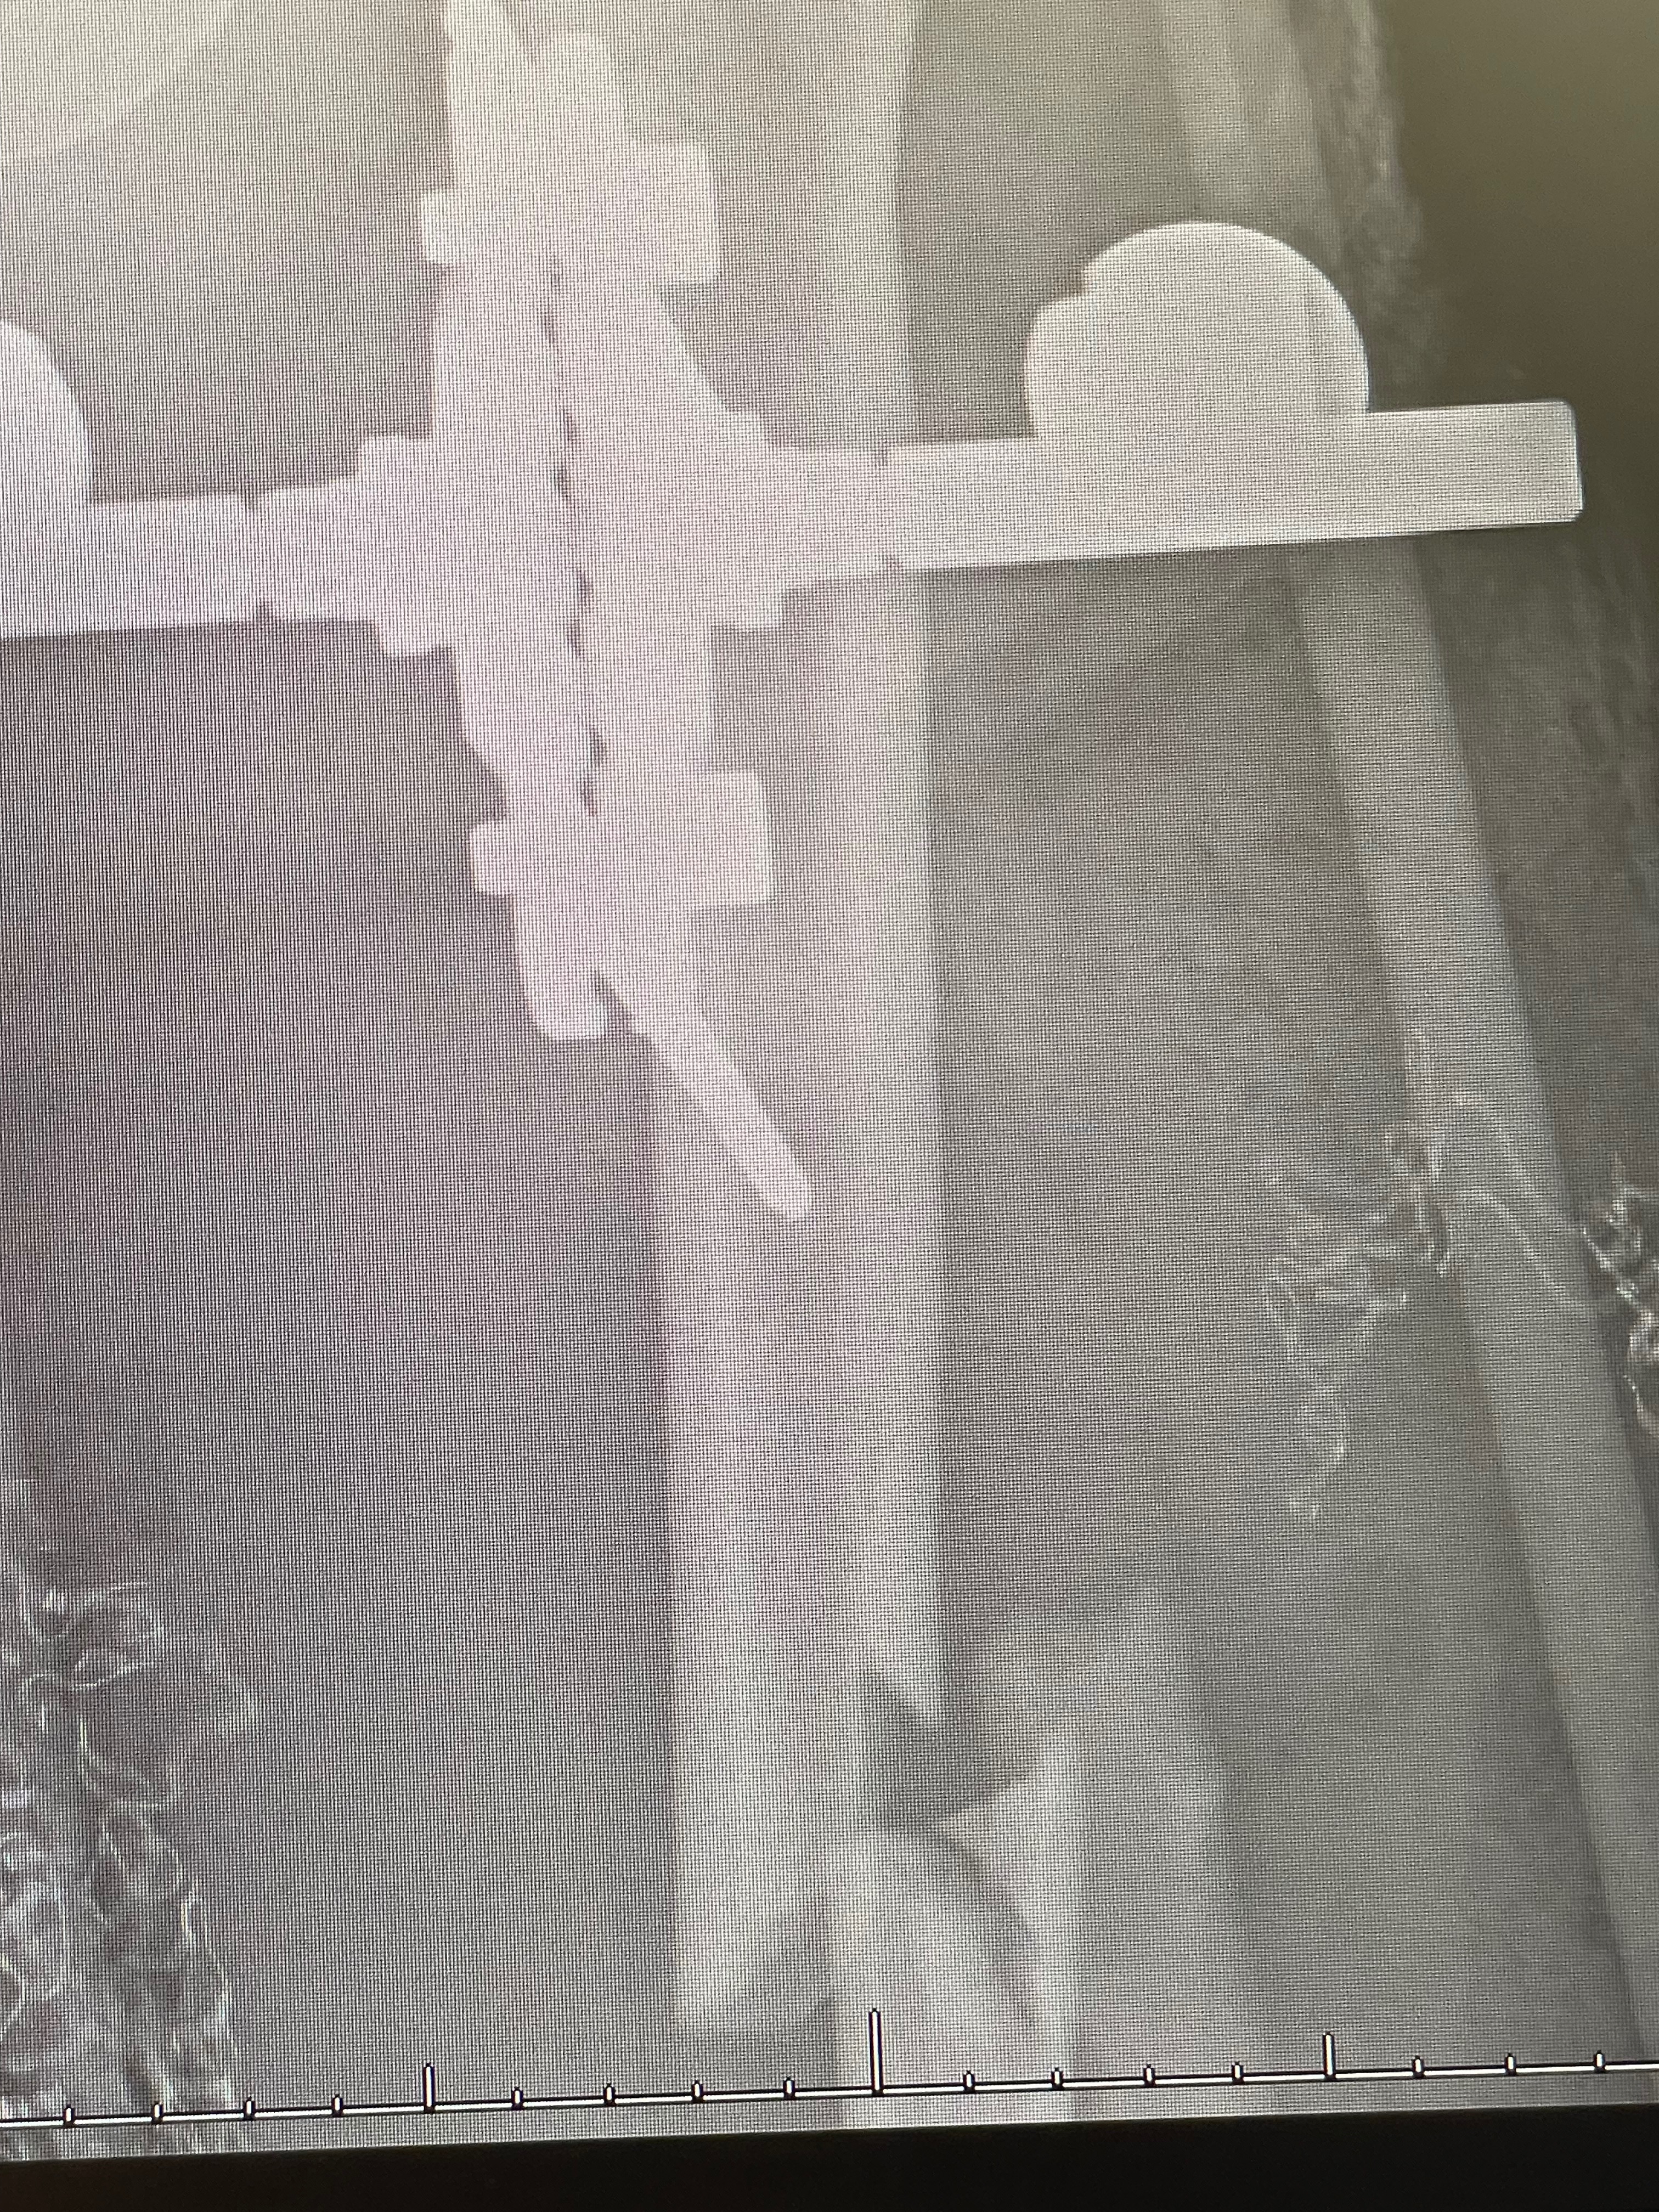

Hi, I’m Steph, a longtime friend of Kevin. On February 18th, while skiing in Park City, Kevin suffered a devastating ski accident that left him critically injured and fighting for his leg. I’m sharing his story to rally support for him, his wife Carolyn, and their daughter Frieda during this unimaginable time.

The road ahead will be long and incredibly challenging. Kevin is expected to undergo multiple surgeries and faces a lengthy recovery, leaving him unable to work for the foreseeable future. This sudden and life-changing event has placed an overwhelming emotional and financial burden on his family.